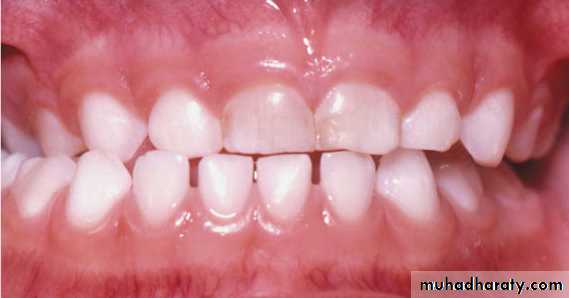

True unilateral crossbite